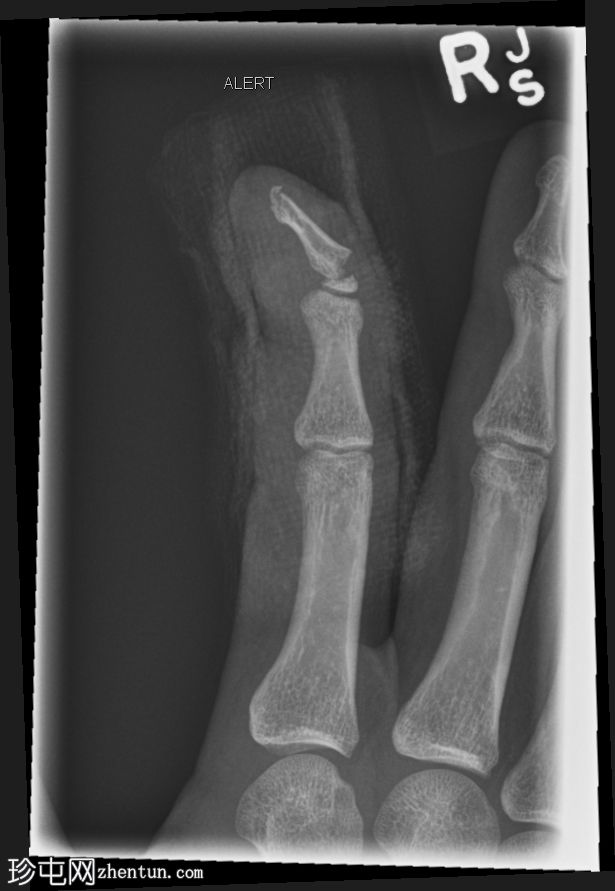

正位片

右食指远节指骨基底部横向移位骨折,伴有背侧成角,最符合成人型Seymour骨折。指尖小骨折。